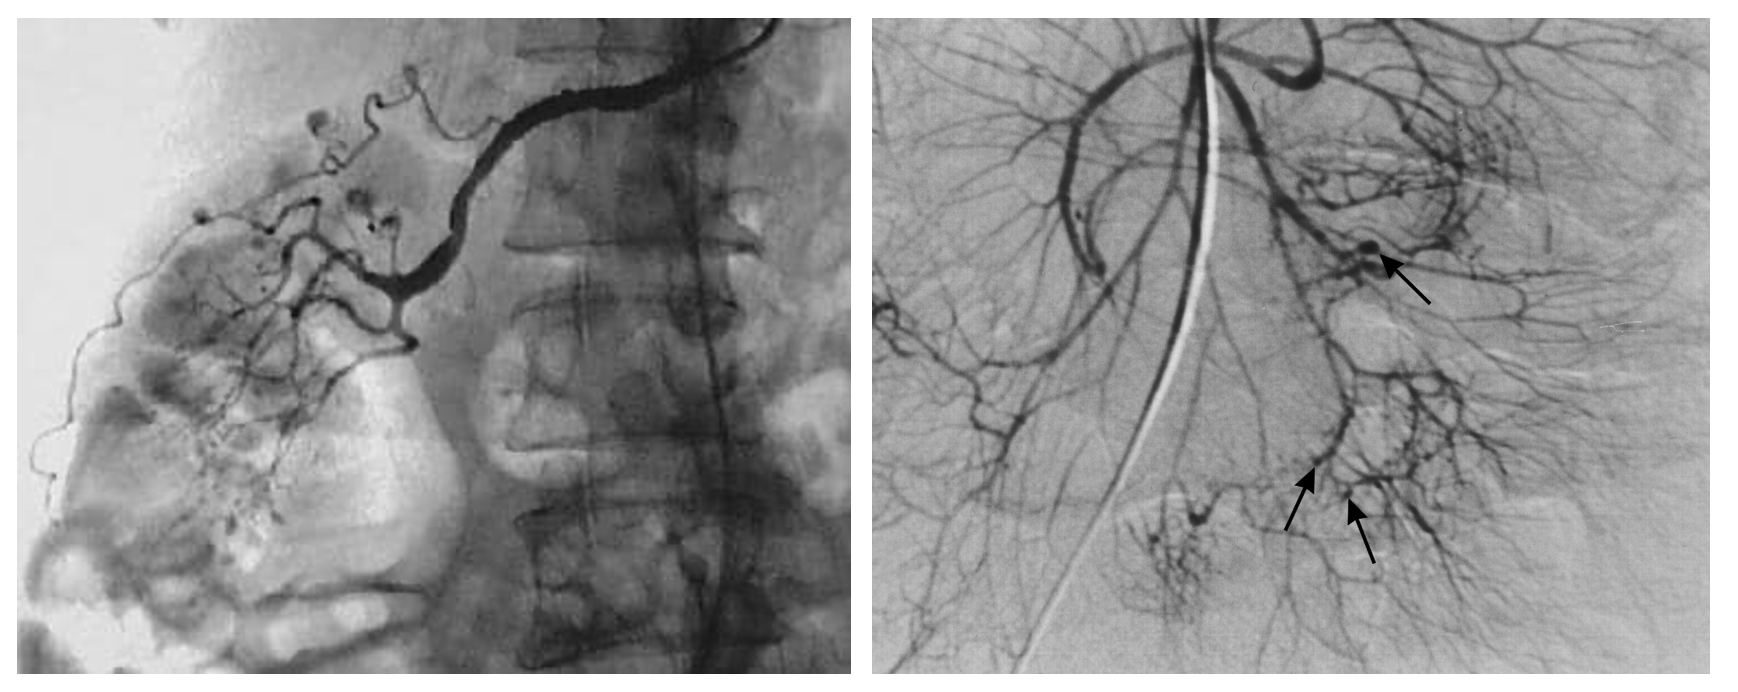

• 혈관 조영술: 신장/장간막 동맥작은 동맥류 (microaneurysms, bead on a string), 폐혈관은 정상